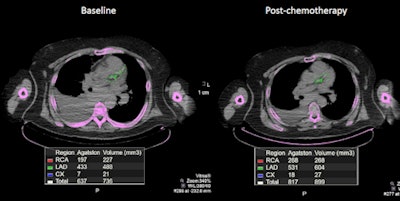

By comparing baseline and follow-up coronary calcium scores from PET/CT scans of lymphoma patients after chemotherapy, researchers say they can better follow the cancer treatment's debilitating impact on the heart, and perhaps get a better handle on possible cardiotoxicity.

The researchers reviewed a total of 375 PET/CT scans and extracted calcium scores from coronary arteries using the low-dose (approximately 3 mSv) CT portion before and after chemotherapy.

When reviewing the results for all 89 patients, the researchers found a statistically significant increase in coronary calcium scores after chemotherapy, with an average gain of 118% from baseline to the postchemotherapy results (p = 0.0124).

As one might expect, the 27 patients with calcium scores greater than 10 at baseline were most responsible for the statistically significant increase in calcium deposition due to chemotherapy (p = 0.025), with an average gain of 651% from baseline to the postchemotherapy results.

Among the 62 patients with no calcium deposition at baseline, there was no statistically significant increase in their calcium score after therapy (p = 0.147). The average gain in calcium score from baseline to the postchemotherapy results was 39%.